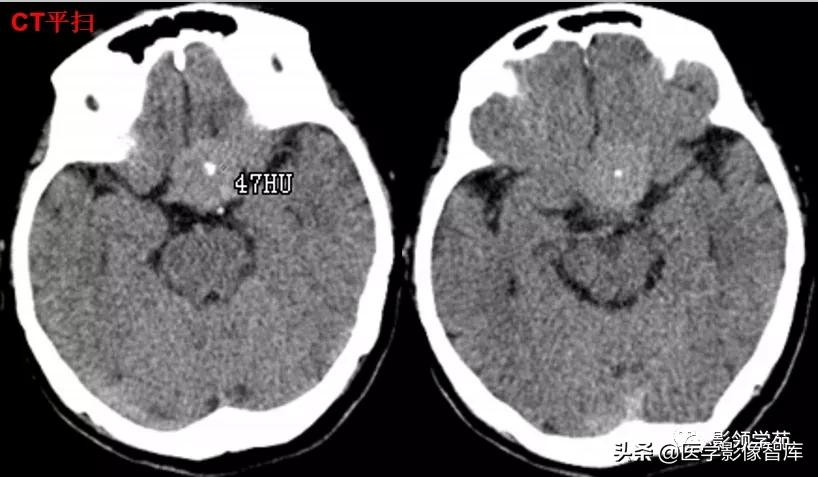

女 72岁,发现糖尿病3年余

鞍上区见一团块状稍高密度影,边界尚清,密度均匀。

鞍上右上方见一类椭圆形流空影。

病灶明显强化(瘤内血栓未强化),边界清楚,与右侧颈内动脉海绵段分界不清。垂体大小、形态未见异常。